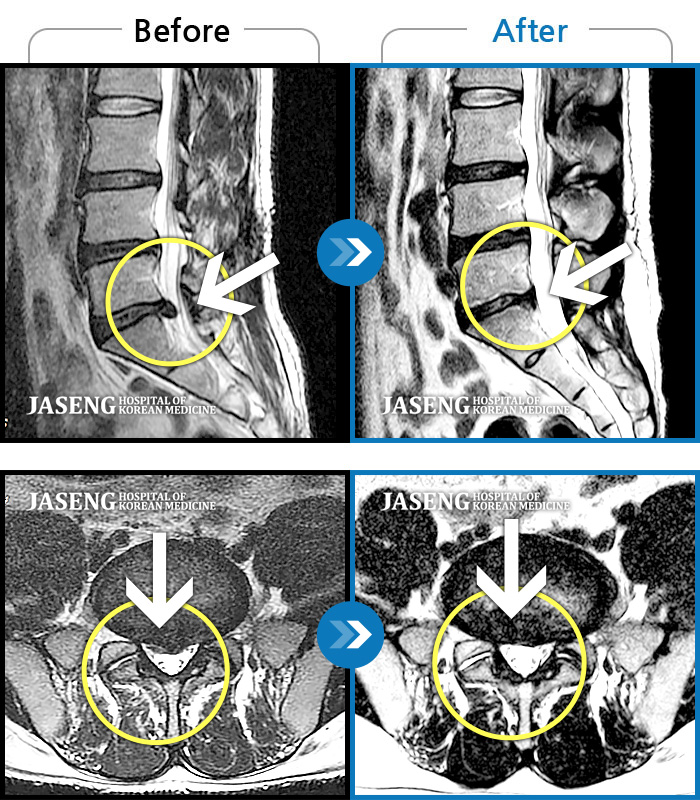

Before

After

허리 통증이 심해 어떤 자세도 힘들며, 우측 다리쪽으로 저리고 통증이 내려온다.

2021.10.26 ~ 2022.04.09